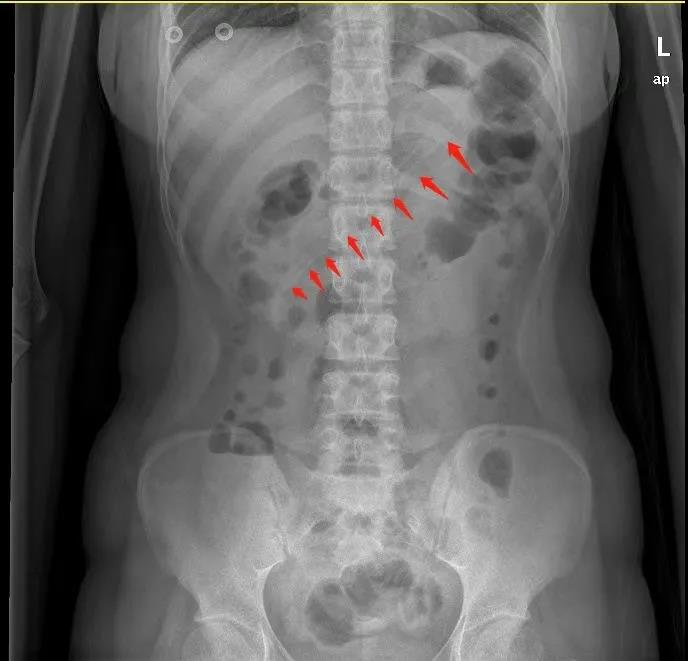

腹部X线检查显示,小李胃中的勺子长达17厘米,因此胃镜下取异物有较大的难度。但如果不取出,患者可能会出现消化道梗阻、出血和穿孔等并发症。因此,胃镜下取出异物势在必行。

通过胃镜,一进入胃腔就能看到一根长长的塑料勺子横跨在胃体至十二指肠球部。

历经40分钟,一根长约17cm的粉色塑料勺子终于从胃内取出了。

▲术后取出的约17厘米长的勺子